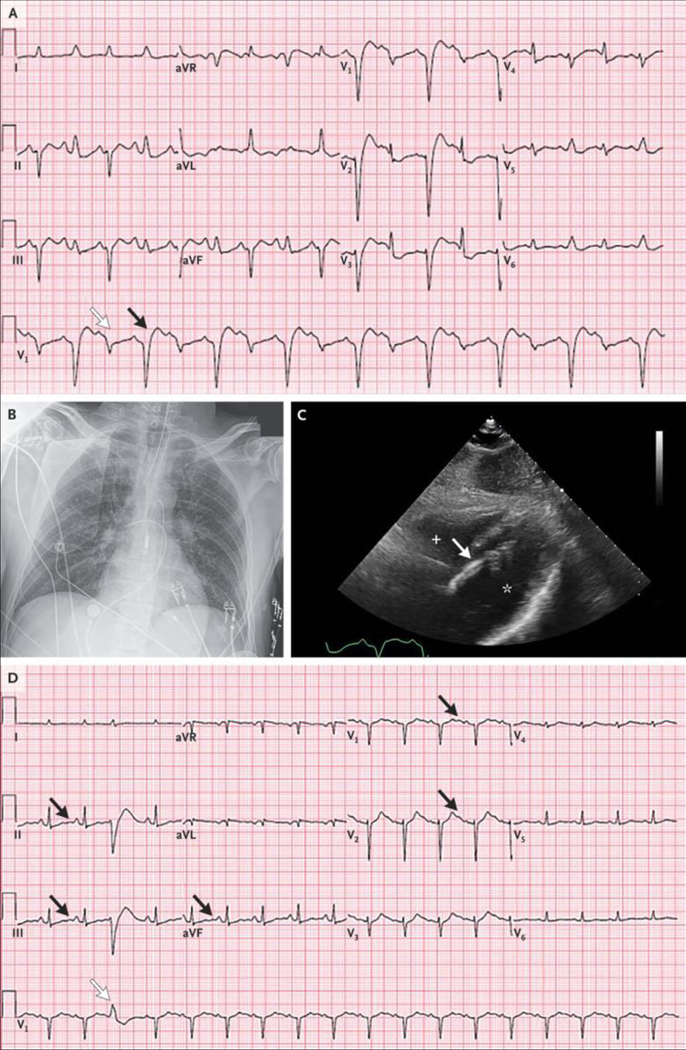

An electrocardiogram (ECG) (Figure 1A) showed uncertain atrial activity; a regular accelerated idioventricular rhythm at a rate of 70 beats per minute, with a very wide QRS complex and multifocal premature ventricular contractions; possible elevations of the ST segment in leads aVR, aVL, and V1; and the presence of U waves.

Figure 1.

Initial ECGs, CT Scan of the Head, and Cardiac Catheterization Studies. Electrocardiograms (ECGs) obtained on presentation (Panel A) and after the return of spontaneous circulation (Panel B) show uncertain atrial activity; a regular accelerated idioventricular rhythm at a rate of 70 beats per minute, with a very wide QRS complex and multifocal premature ventricular contractions (white arrows); possible elevations of the ST segment in leads aVR, aVL, and V1; and the presence of U waves (black arrows). An axial computed tomographic (CT) image of the head (Panel C), obtained without the administration of contrast material, was normal, without evidence of infarct, intracranial hemorrhage, or mass lesions. Images from a left coronary angiogram (Panel D) and a right coronary angiogram (Panel E) show only minimal luminal irregularities.

Initial laboratory test results obtained 25 minutes after the patient arrived at this hospital are shown in Table 1. Cardiac ultrasound images obtained at the bedside showed marked global left ventricular dysfunction. Spontaneous circulation was restored; the heart rate was 108 beats per minute and the blood pressure 139/92 mm Hg while the patient was receiving intravenous epinephrine and norepinephrine. A repeat ECG (Figure 1B) showed findings similar to those seen on presentation.

Computed tomography of the head (Figure 1C), performed without the administration of intravenous contrast material, revealed preservation of differentiation between gray and white matter, without evidence of territorial infarct, intracranial hemorrhage, or mass lesions.

The patient was transferred to the cardiac catheterization laboratory, where a transaortic percutaneous ventricular assist device was placed through the femoral artery, and thereafter, the patient was weaned from epinephrine and norepinephrine. Coronary angiography (Figure 1D and 1E) revealed only minimal luminal irregularities (see Videos 1 and 2, available with the full text of this article at NEJM.org). Subsequent catheterization of the right and left sides of the heart revealed a right atrial pressure of 13 mm Hg, a pulmonary capillary wedge pressure of 27 mm Hg, and a left ventricular end-diastolic pressure of 30 mm Hg. The pulmonary arterial oxygen saturation was 85%.